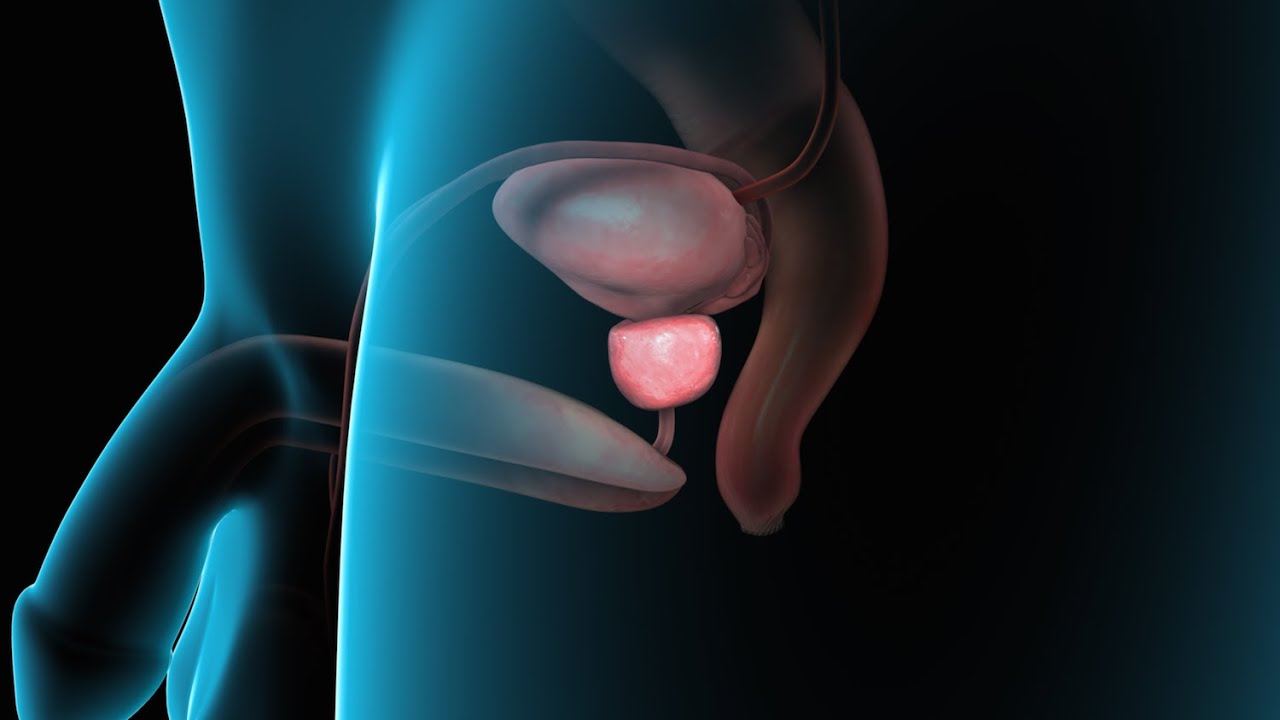

"I had an excellent experience at the urology clinic. The staff was very friendly and professional, and the doctor was knowledgeable and thorough in their examination. I received the care and attention I needed to address my urological concerns, and I highly recommend this clinic to anyone seeking quality